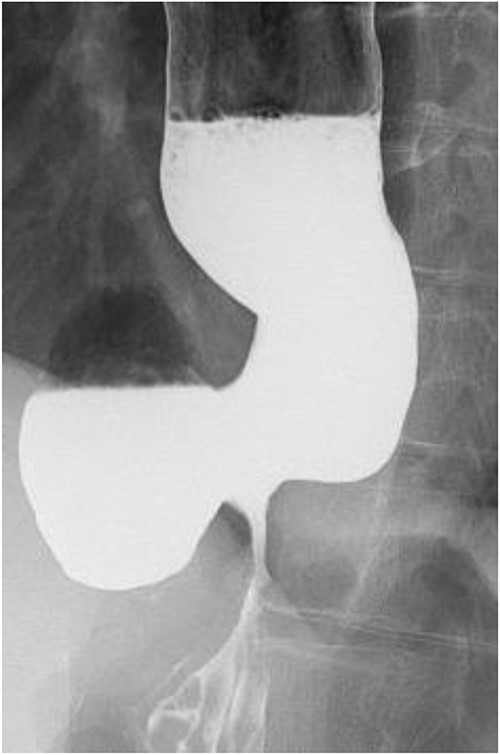

The operative findings showed poor coloration of the vault surrounding by Nissen’s method, so the patient underwent lower esophagogastric resection and interstitial jejunal reconstruction (Fig. 4). The operation time was 230 minutes, and the blood loss was 580 ml. The resection specimen showed diverticulum-like cystic formation due to the esophageal mucosal dilatation at the esophagogastric junction and the entrapment of the esophageal mucosa associated with the outer membrane adhesion (Fig. 5). The postoperative course was generally favorable. Esophageal fluoroscopy on the seventh postoperative day showed no evidence of stricture. The contrast medium drained into the stomach without stagnation (Fig. 6). On the 13th postoperative day, she developed dumping-like symptoms, which improved with dietary guidance. Besides that, the patient had no other significant problems and was discharged from the hospital on the 19th day. She is now six years postoperatively and has gained 6 kg compared to her preoperative weight. The patient is doing well.

Postoperative esophageal fluoroscopy. No stenosis findings or stagnation of contrast media was observed.